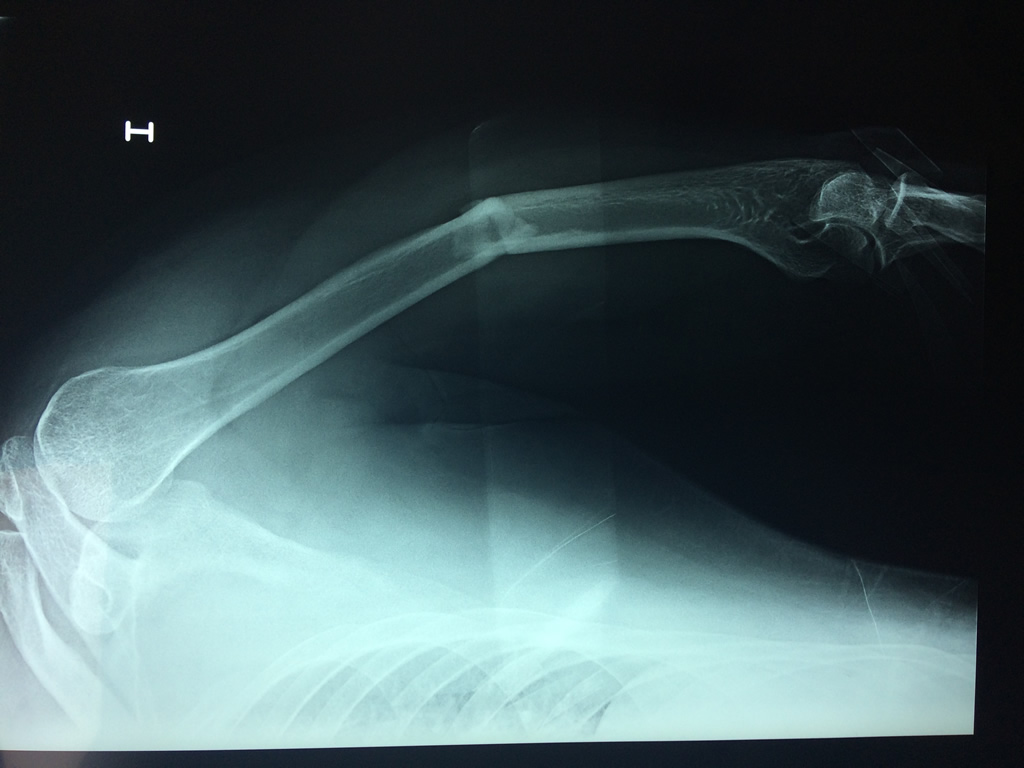

Húmero